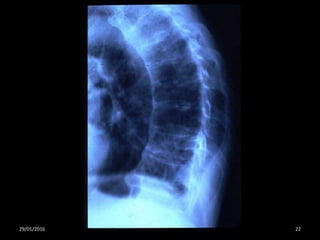

Cuadro clínico

Dolor de espalda

Pérdida de altura

Reducción de la función pulmonar

deformidad

29/01/2016 22

Osteoporosis y fracturas. Una perspectiva ortopédica. Iniciativa de Cirujanos Ortopédicos. Fundación Internacional de la

Osteoporosis International Society for Fracture Repair. Década del hueso y la articulación.